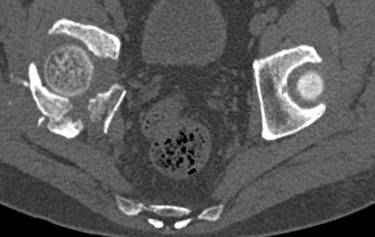

высылаю дополнительно сканы.

Судя по представленным реконструкциям (не очень хорошего качества - много наводок)

мы имеем дело с полупоперечным переломом у которого отломался задний край или его отломали, превратив перелом в полный двухколонный.

По отдельным срезам и тем более по реконструкции трудно судить о сращении крыла и задней колонны с осевым скелетом.

В большинстве случаев при двухколонных переломах

в итоге получается прочный бублик с дыркой. При эндопротезировании в дырку помещается головка, а чашка должна неплохо заклиниться в бублике.

Главное, чтобы бублик не был разорван, что не очень понятно на представленных снимках.

Все выступающие коллеги высказались насчет необходимости стандартных снимков по Judet, потому что для определения тактики лечения переломов вертлужной впадины 3Д снимки малоинформативны.

Из того минимума, что представлено, мне кажется, мы имеем дело с двухколонным переломом вертлужной впадины. Обычно медиальный (центральный) "вывих" головки встречаются в сложных двухколонных переломах со смещением.